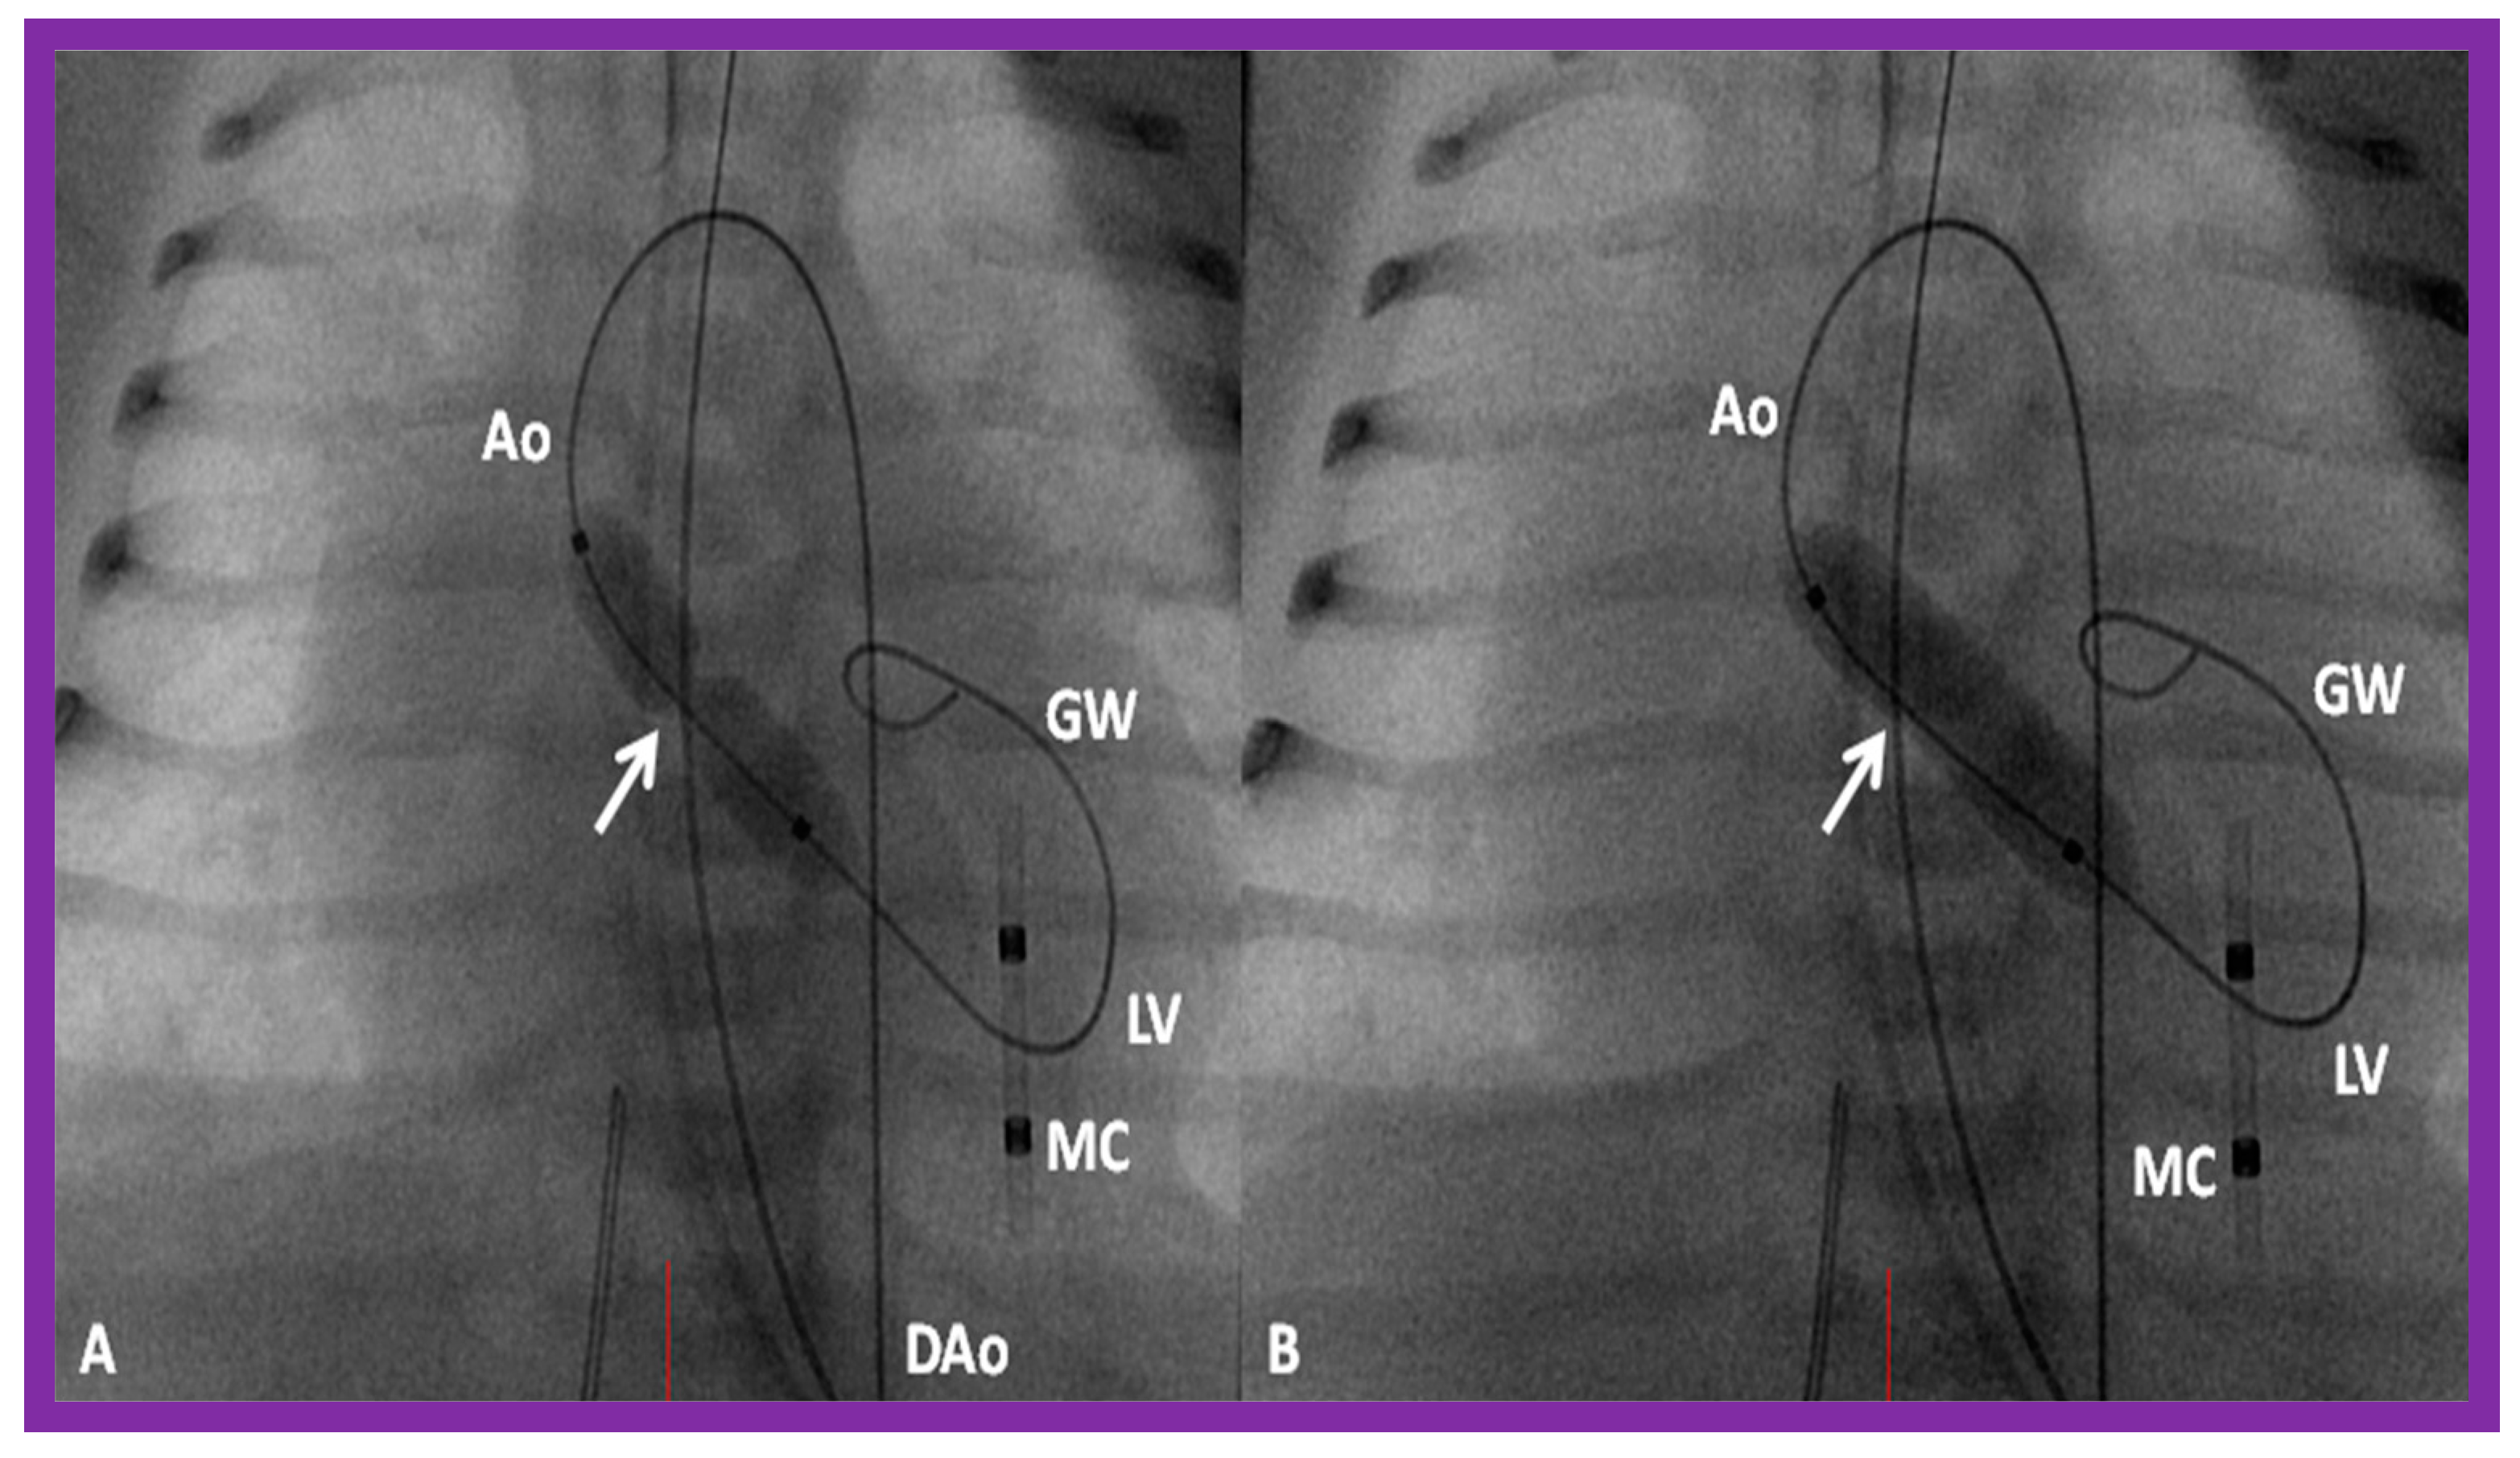

Aortic Stenosis in the Fetus

3.3. Aortic Coarctation, Native